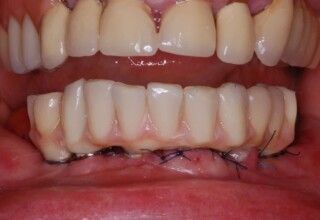

Lower jaw: extractions, direct implant placement and immediate loading (same day) with a transitional bridge.

Upper jaw: Sequential extractions, sequential implant placement and gradual incorporation in the temporary bridge so that the patient was never left without fixed teeth. The aim of the above approach was to have the patient in continuous functional and aesthetic reconstruction, without immediate loading due to anatomical restrictions. Old smiling photos of the patient were used because the natural shape of the teeth was completely lost due to repetitive prosthetic attempts. Tooth relationship and teeth-lip support was transferred to the temporary restorations. Two different transitional bridges were needed to fully estimate phonetics, mastication and esthetics. After the necessary adjustments were finalized, the temporary bridge was used as a guide for the permanent bridges.